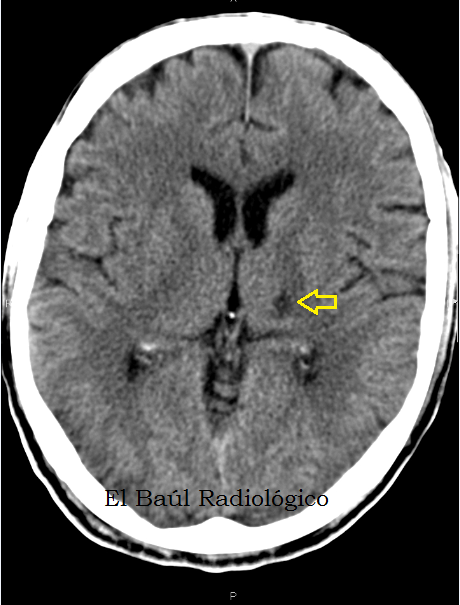

PDF | Reportamos el caso de un paciente con enfermedad diabética tipo 1 que sufrió un ACV isquémico lacunar talámico derecho y. A watershed stroke or watershed infarct is defined as a brain ischemia that is localized to the . as total anterior circulation infarct (TACI), partial anterior circulation infarct (PACI), lacunar infarct (LACI) or posterior circulation infarct ( POCI). A stroke is a medical condition in which poor blood flow to the brain results in cell death. .. This subset of cryptogenetic stroke is defined as a non-lacunar brain infarct without proximal arterial stenosis or cardioembolic sources. About one out of.

The term was penned by Charles Miller Fishera Canadian neurologist, who described “lacunes” Latin: Retrieved 30 June And in some of these persons, strokes have been found which were then treated with thrombolytic medication. However, stroke can occur at any age, including in childhood. This definition was supposed to reflect the reversibility of tissue damage and was devised for the purpose, with the time frame of 24 hours being chosen arbitrarily. This sets off a series of interrelated events that result in cellular injury and death.

To quiz yourself ac this article, log in to see multiple choice questions. Archived PDF from the original on 19 October Watershed strokes are named because they affect the distal watershed areas of the brain. The term cerebrovascular accident was introduced inreflecting a “growing awareness and acceptance of vascular theories and Furthermore, bilateral watershed strokes are associated with poor short-term outcomes and are most reliably observed by llacunar imaging MRI.